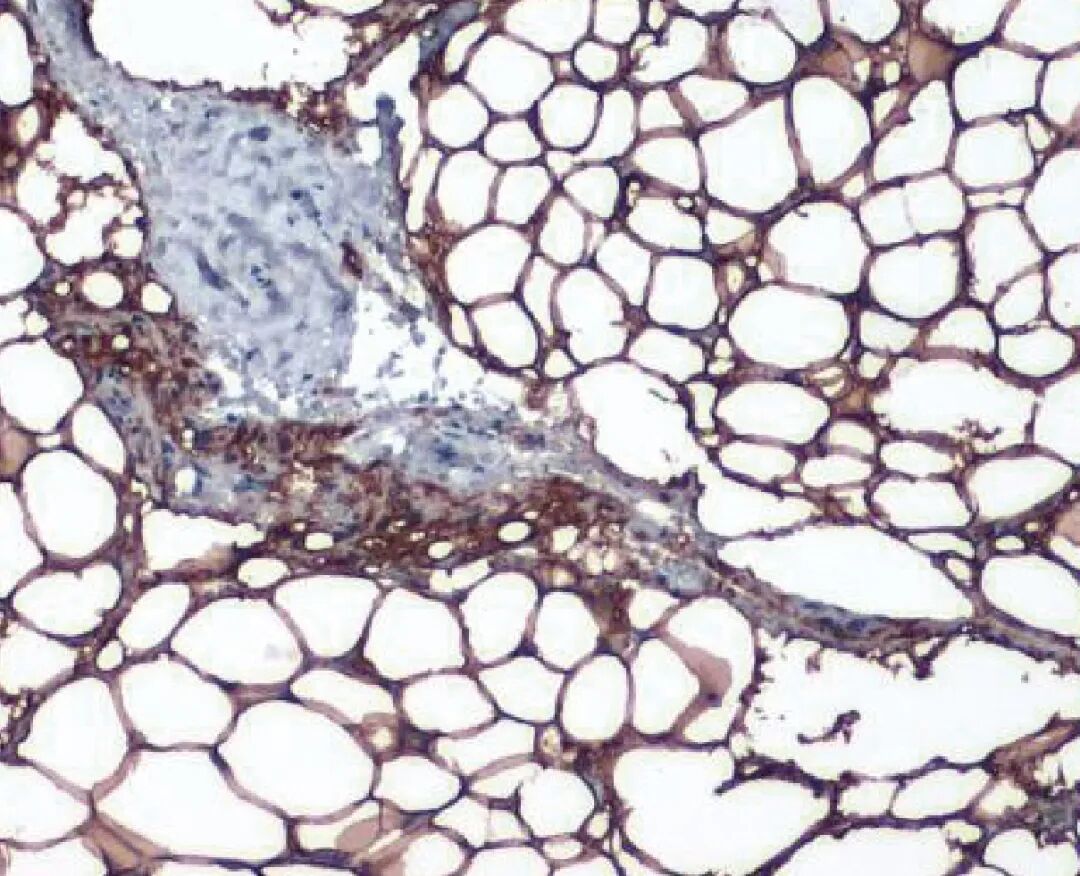

脂肪细胞也是高度活跃的分泌细胞,产生的蛋白质和激素的功能远超过新陈代谢。在长期的正能量平衡条件下,脂肪细胞会扩大细胞大小和数量,以补偿增加脂质储存的需求,当超过最大的脂肪组织储库----皮下脂肪组织的储存能力时,进一步的热量过载会导致异位组织(肝脏、骨骼肌、和心脏)以及内脏储库中的脂肪积聚,异位组织中过多的脂质蓄积会导致局部炎症 (3),脂肪组织炎症的诱因可能来自肠道来源的物质、饮食成分和代谢产物,另外,肥胖中脂肪组织的迅速膨胀可能会引起触发炎症反应的内在信号,这些信号包括由细胞与细胞外基质之间相互作用所引起的脂肪细胞死亡或缺氧(图二)。 |

| 图二: 通过脂肪细胞肥大引起的不健康扩张,促进了肥胖相关的代谢并发症 |